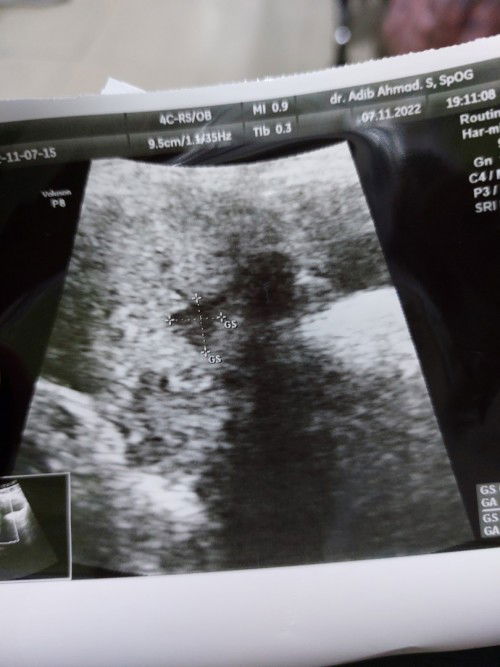

Keluar darah hamil 6 minggu 3hari

Hay bund,,mngkin ada yang udh lihat pertanyaanku kmrin yg pas usg 5week 5hari blm klihatan apa2,,td mlm aku alami keram perut bagian kiri,dan skrg aku alamin flek bund pas pipis..bbrpa menit kmudian kluar darah seger... ada yg pernh ngalamin gk? Apa ini tanda keguguran?

Hamil BO Dan sekarang hamil lagi 6week

Bund cerita sedikit saya bulan juli hamil bo trus harus kuret,skrg lg hamil lagi sudah 6week dan pas periksa ke dokter blm ada terlihat kantung maupun janin,,aku khawatir bnget bun takut terjadi lagi hamil bo nya..ada yg sama gak bun kyk saya? 6 week bkm trlihat apa2